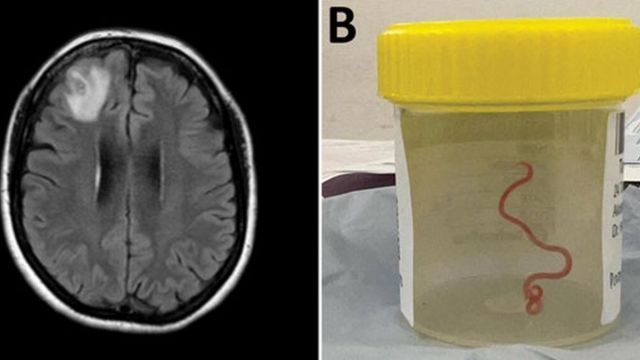

أعلن العلماء أنه تم العثور على دودة طولها 8 سم حية في دماغ امرأة أسترالية، إذ تم إدخال المريضة إلى المستشفى في أواخر جانفي 2021، وكشف الفحص لاحقاً عن “تشخيص غريب داخل الفص الجبهي الأيمن من الدماغ” ولم يتم الكشف عن حالتها إلا بعد إجراء خزعة في جوان 2022.

وأكد الأطباء أن السيدة تتعافى بشكل جيد بعد استخراج الدودة.